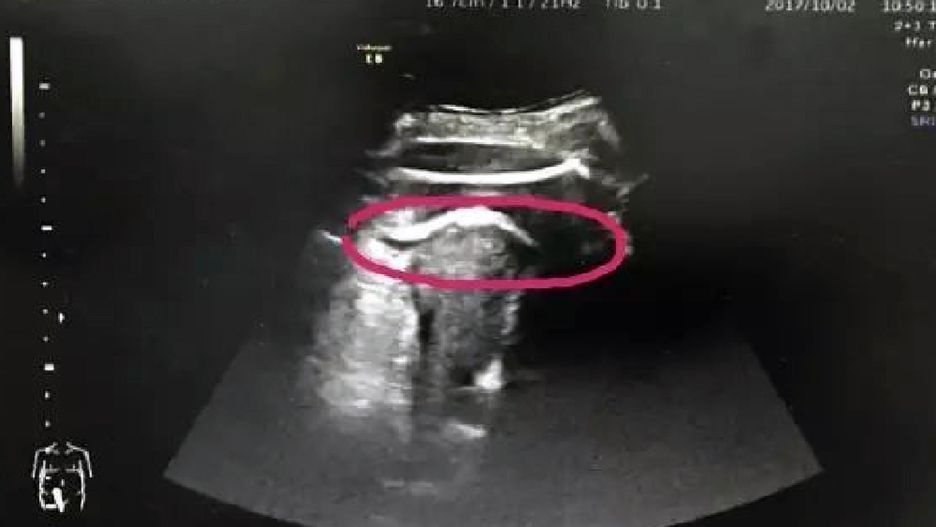

Podobny przypadek do tego z Chin miał miejsce we Francji, w grudniu ubiegłego roku. 33-letnią kobietę poddano cesarskiemu cięciu po tym, jak nogi płodu - pozostając w worku owodniowym - przebiły ściankę macicy. Kobieta już raz wcześniej rodziła, także przez cesarskie cięcie. Po operacji oboje, mama i jej mocno kopiący syn, mieli się dobrze.

© NEJM, Pierre-Emmanuel Bouet, Centre Hospitalier Universitaire d'Angers